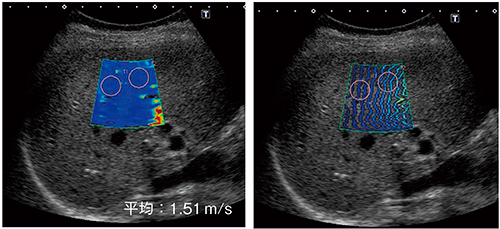

肝生検でF1,A1(慢性肝炎)と診断された症例1では,剪断速度表示モードできれいに青くカラー表示された部分では,等高線表示モードでも均一に波が進んでいることが確認できた(図8)。血管の部分は,カラー表示が抜けている。

図8 症例1:F1,A1(慢性肝炎)

生検でF3,A1と診断された症例2では,剪断速度表示モードでの色調が,症例1よりやや黄味がかっていた(図9)。等高線の幅も症例1よりやや広く表示されており,剪断速度の測定値は2.3m/sであった。

図9 症例2:F3,A1

F1症例と比べて色が明るく,等高線の間隔も広い。